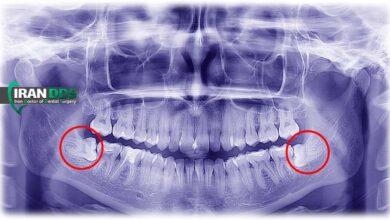

جراحی دندان عقل نهفته؛ مزایا، معایب و مراقبتها

دندان عقل نهفته یکی از شایعترین مشکلات دهانی است که معمولاً در سنین 17 تا 25 سالگی بروز میکند. این…